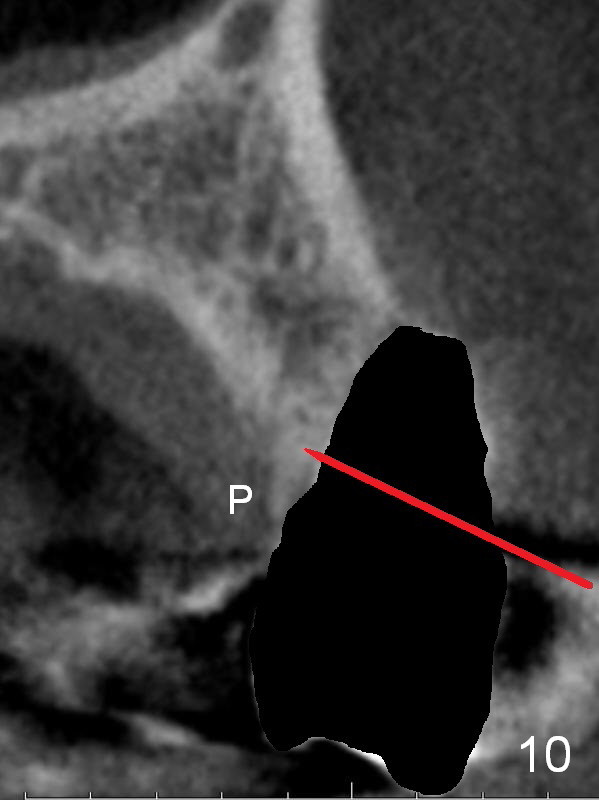

After extraction, the bottom of the socket must be oblique (Fig.9 arrowheads). As usual, osteotomy is initially at the junction of palatal (Fig.10 P) 1/3 and middle 1/3 perpendicular to the plate.  Once the drill gets engaged, the trajectory is to be changed (Fig.11 curved arrow) so that the apical end of the osteotomy (red line) is as close to the buccal plate (B) as possible.  The purpose is to keep the palatal end of the osteotomy as palatal as possible.  In spite of the effort, an angled abutment is expected, as large as 20 degree (Fig.8 purple angle).